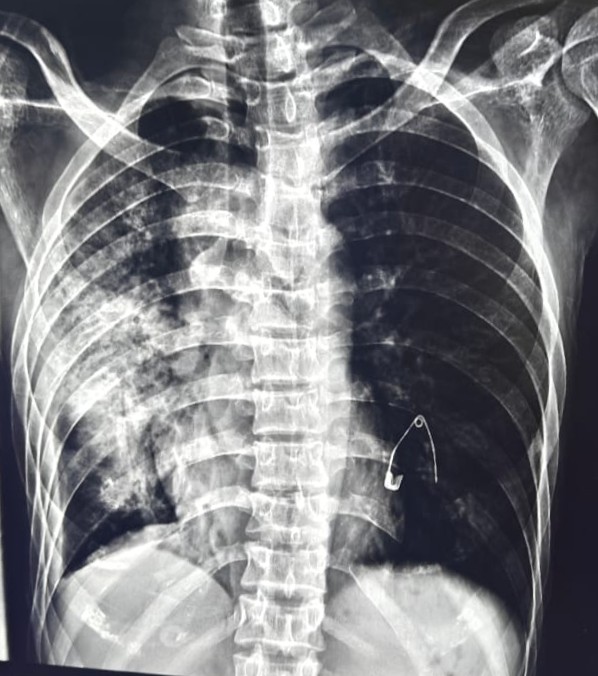

| 206 | IGGMC, Nagpur, Nagpur | P2 | 29-4266 | SHUBHAM URKUDE | Consent taken on Paper | 30 Yrs. |

Provisional Diag : PTB?

Final Diag : CLINICALLY DIAGNOSED PTB WITH OLD EPTB WITH LOSS TO FOLLOW UP IN CHRONIC ALCOHOLIC |

TB Case (Confirmed) | BILATERAL MIDDLE ZONE HAZZINESS/CONSOLIDATION | Abnormality visible on x-ray |